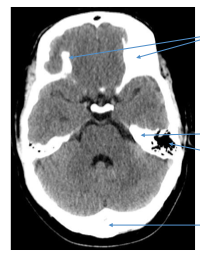

Label the image

What type of image is this?

Why is there asymmetry?

The image is a CT scan, top two arrows point towards bone as bone appears white in CT scans.

The asymmetry is due to the plane of the cross secton and isn’t actually pathology but the plane at which it was taken.

Next two arrows are pointing to the petrous portion of the temporal bone and the mastoid air cells.

Last arrow is poiting towards the occipital bone.